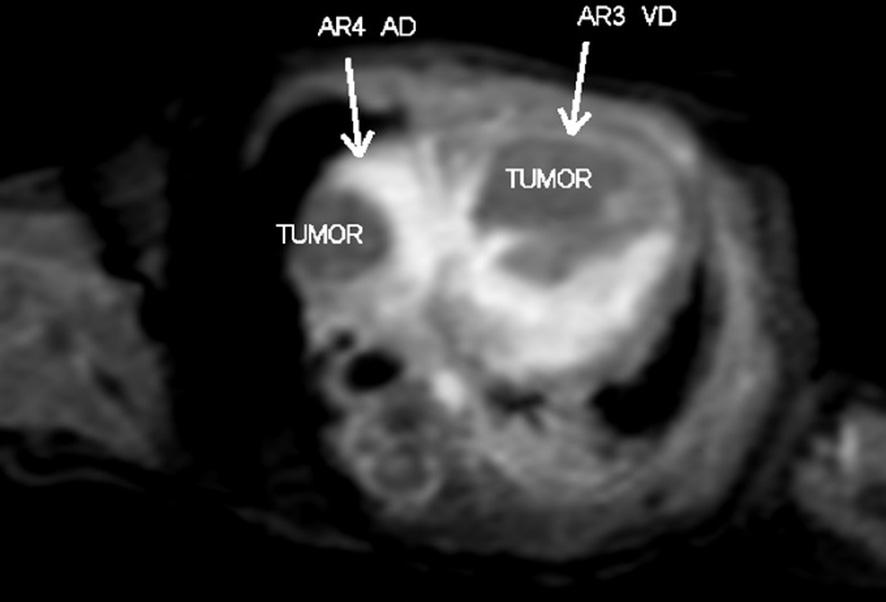

- El primer caso se trata de una paciente de 20 años de edad, sin antecedentes heredofamiliares de importancia, la cual inicia control de embarazo de alto riesgo en tercer nivel por múltiples amenazas de aborto. Derivada a nuestro hospital a las 36 semanas de gestación, realizándose el primer ecocardiograma prenatal por parte de nuestro servicio detectando tumores cardiacos compatibles con rabdomiomas, con imagen ecogénica en aurícula derecha de 18 mm y en ventrículo derecho de 20 mm con septum interventricular de 8 mm (Fig. 1), sin datos de obstrucción al tracto de salida, por lo que se decide continuar con el embarazo. Nace por cesárea, sin complicaciones. Se realiza ecocardiograma posnatal de control con los hallazgos previos, reportando tumoración a nivel de la cava superior de 13 x 18 mm, tumoración en surco atrioventricular de 15.4 x 4.5 mm, en ventrículo derecho con tumoración de 17.4 x 22 mm, siendo bilobulado, a nivel del ventrículo izquierdo con múltiples tumoraciones adheridas al septum y a la pared anterior la mayor de 7.7 x 8.2 mm (Fig. 2), corroboradas por resonancia magnética (Fig. 3). Debido a la asociación de tumores intracardiacos con esclerosis tuberosa fue valorado por el Servicio de Neurología, en donde mediante la realización de resonancia magnética de encéfalo se evidencia lesión nodular intraaxial en el giro recto derecho y nódulos subependimarios en ambos ventrículos laterales (Fig. 4), con hallazgos referidos que se encuentran dentro del espectro de esclerosis tuberosa. Se mantiene en vigilancia, en control por la consulta externa de dicho servicio.

Figura 3 Imagen posnatal de la resonancia magnética en secuencia de sangre blanca, eje cuatro cámaras, donde se observan imágenes isointensas en aurícula y ventrículo derechos, característica de rabdomiomas.